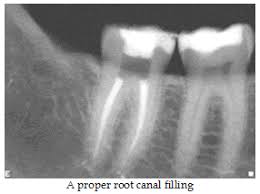

If the root canals are able to be fully cleaned and sealed and the tooth properly restored then treatment has a very high success rate. The treatment may take several visits to complete with temporary fillings and dressings placed in the tooth between visits. Antibiotics are sometimes prescribed when an infection is present.